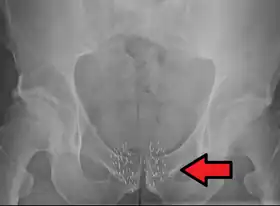

![]() Arrow points to brachytherapy beads used to treat prostate cancer. | |